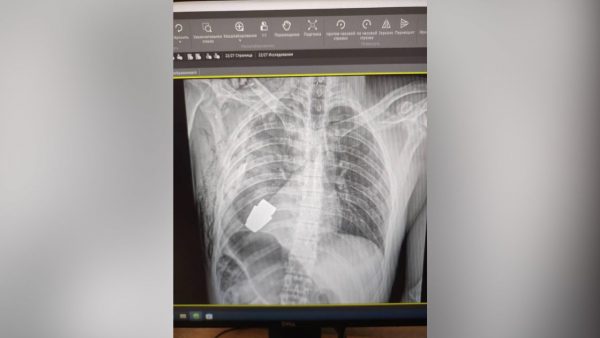

Άγνωστο πώς κατέληξε εκεί

Στο νοσοκομείο μία κοπέλα